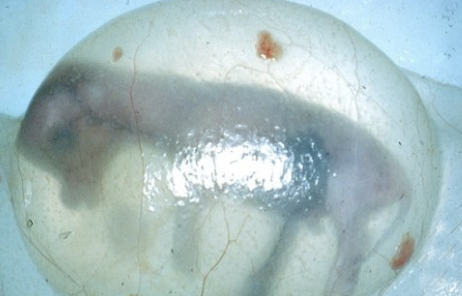

2. amniotic vesicle (feels like a grape)

when is the amniotic vesicle palpable?

after 28 days, is turgid, spherical until day 55

what may occur if the amniotic vesicle is roughly palpated between days 32-44?

may be associated with atresia coli of fetus